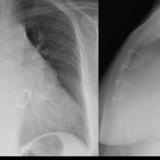

calcif Ao valve

Ao valve calcif (lat only)